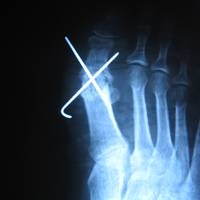

• Αρθρίτις μεταταρσιοφαλαγγικής